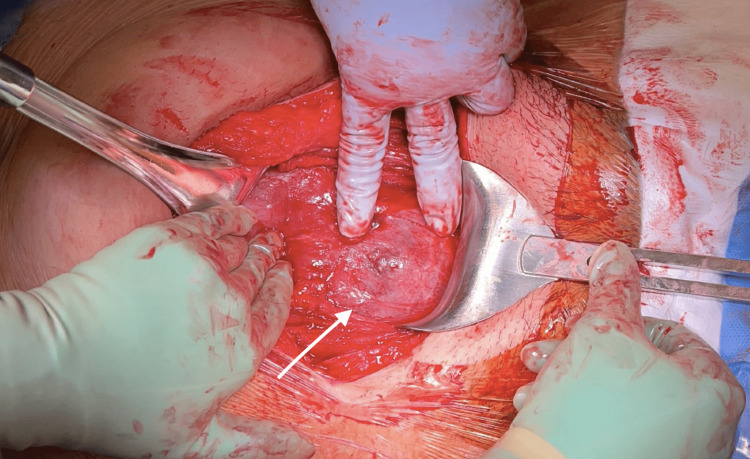

Due to concern for uterine rupture, the decision was made to proceed with repeat cesarean delivery at 31 weeks. Magnesium sulfate 4 g IV bolus was started at this time for neuroprotection. Intraoperatively, she was noted to have a 5x3 cm uterine dehiscence (Figure 4).

Figure 4. Operative view of uterine dehiscence.

Operative view of uterine dehiscence, measuring 5x3 cm, after entering the peritoneum with bladder adhesions.